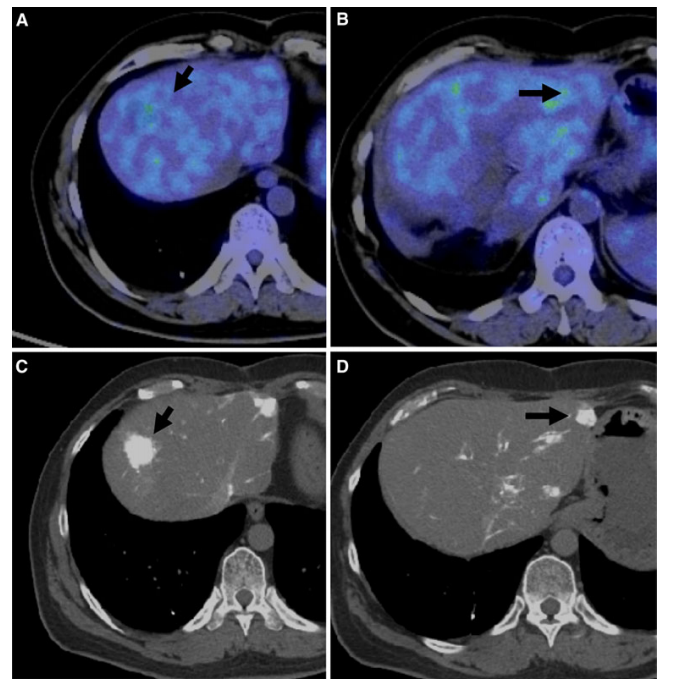

(图6)1例肝脏增强CT发现右肝高强化结节(A),腹膜高强化结节(D)。PET-CT评估发现,两枚结节FDG浓聚明显。该患者合并丙肝,AFP 897ng/ml,最终诊断为HCC合并腹膜转移。